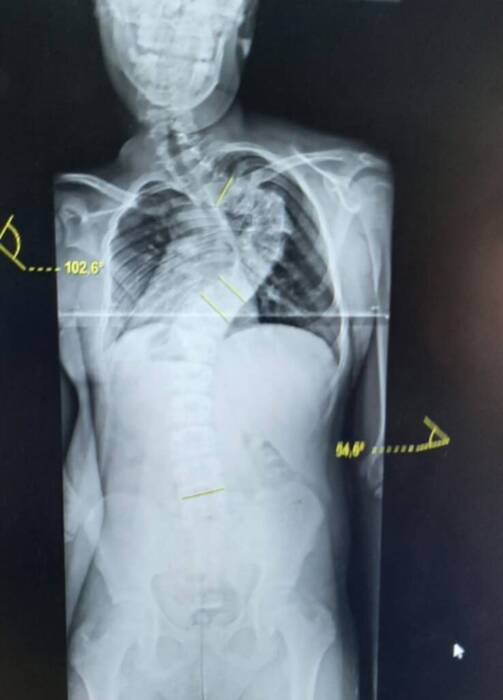

A primeira doença é degenerativa e grave, que faz seus ossos da coluna atrofiarem. A segunda ataca diretamente seu sistema nervoso e também traz grande risco e problemas. Depois de várias consultas, diagnósticos e tudo que a burocracia exige para que a criança fizesse uma cirurgia corretiva e ajudasse a resolver a situação no início, nada foi feito e a doença evoluiu de tal forma, que Isac já estava com dificuldade de respiração.

Lucinei Rodrigues Miguel, agricultora e mãe, viu uma série de pedidos e de falas que a fila de espera estava “andando” e, em um ano sem resposta, resolveu levar o jovem para o Hospital Joana de Gusmão, em Florianópolis, para tentar aliviar as dores e salvar a vida do seu filho, pois a qualquer momento a coluna de Isac pode estourar e perfurar algum órgão.

“A Secretaria de Saúde, de Morro Grande trouxe a gente; vim com a cara e a coragem, direto para a emergência do Hospital, na capital. Os médicos informaram que agora ele terá que passar por esse processo para ver se obtém alguma melhora na coluna, pois a situação se agravou tanto que, se fosse para a cirurgia ele poderia não sobreviver e, se sobrevivesse, a chance de não ter sucesso e ele ir para cadeira de rodas era muito grande”, contou, emocionada, a mãe.

A cirurgia particular gira em torno de R$ 200 mil, que ajudaria na cifoescoliose, colocando parafusos e hastes de ferro em toda a coluna. Os pais estavam tentando, através de doações, arrecadar o dinheiro, o que não foi possível. Já a segunda doença, precisará de outro tratamento urgente, diante do fato de que a neurofibramatos cria tumores e pode atingir o cérebro.